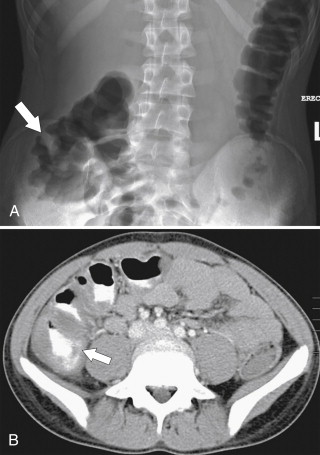

Figure 5-1, Plain abdominal radiograph ( A ) and contrast enema ( B ) in a 4-month-old male infant with constipation ( arrow ) due to Hirschsprung disease.

The aganglionic segment is usually located in the upper rectum or rectosigmoid junction, with the proximal large bowel becoming grossly dilated over many years of partial obstruction. The diagnosis is usually best made by contrast enema studies ( Fig. 5-2 ), even in the neonate, but definitive diagnosis requires rectal biopsy. The stricture is usually identified at contrast enema in the rectosigmoid regions with variable colonic distention proximal to the stricture. The aganglionic segment may not appear as an abrupt transition but rather as an irregular serrated or “sawtooth” appearance, which is characteristic of the disease ( Fig. 5-3 ). Some patients develop an associated colitis, termed “Hirschsprung-associated enterocolitis,” that is characterized by foul-smelling diarrhea. These patients are at risk of perforation because of acute colitis, but subacute forms exist, and contrast enema studies may show the characteristic rectal sawtooth finding.

Figure 5-3, BE in a 3-week-old male neonate with Hirschsprung disease as evidenced by a “sawtooth” rectum ( arrow ).